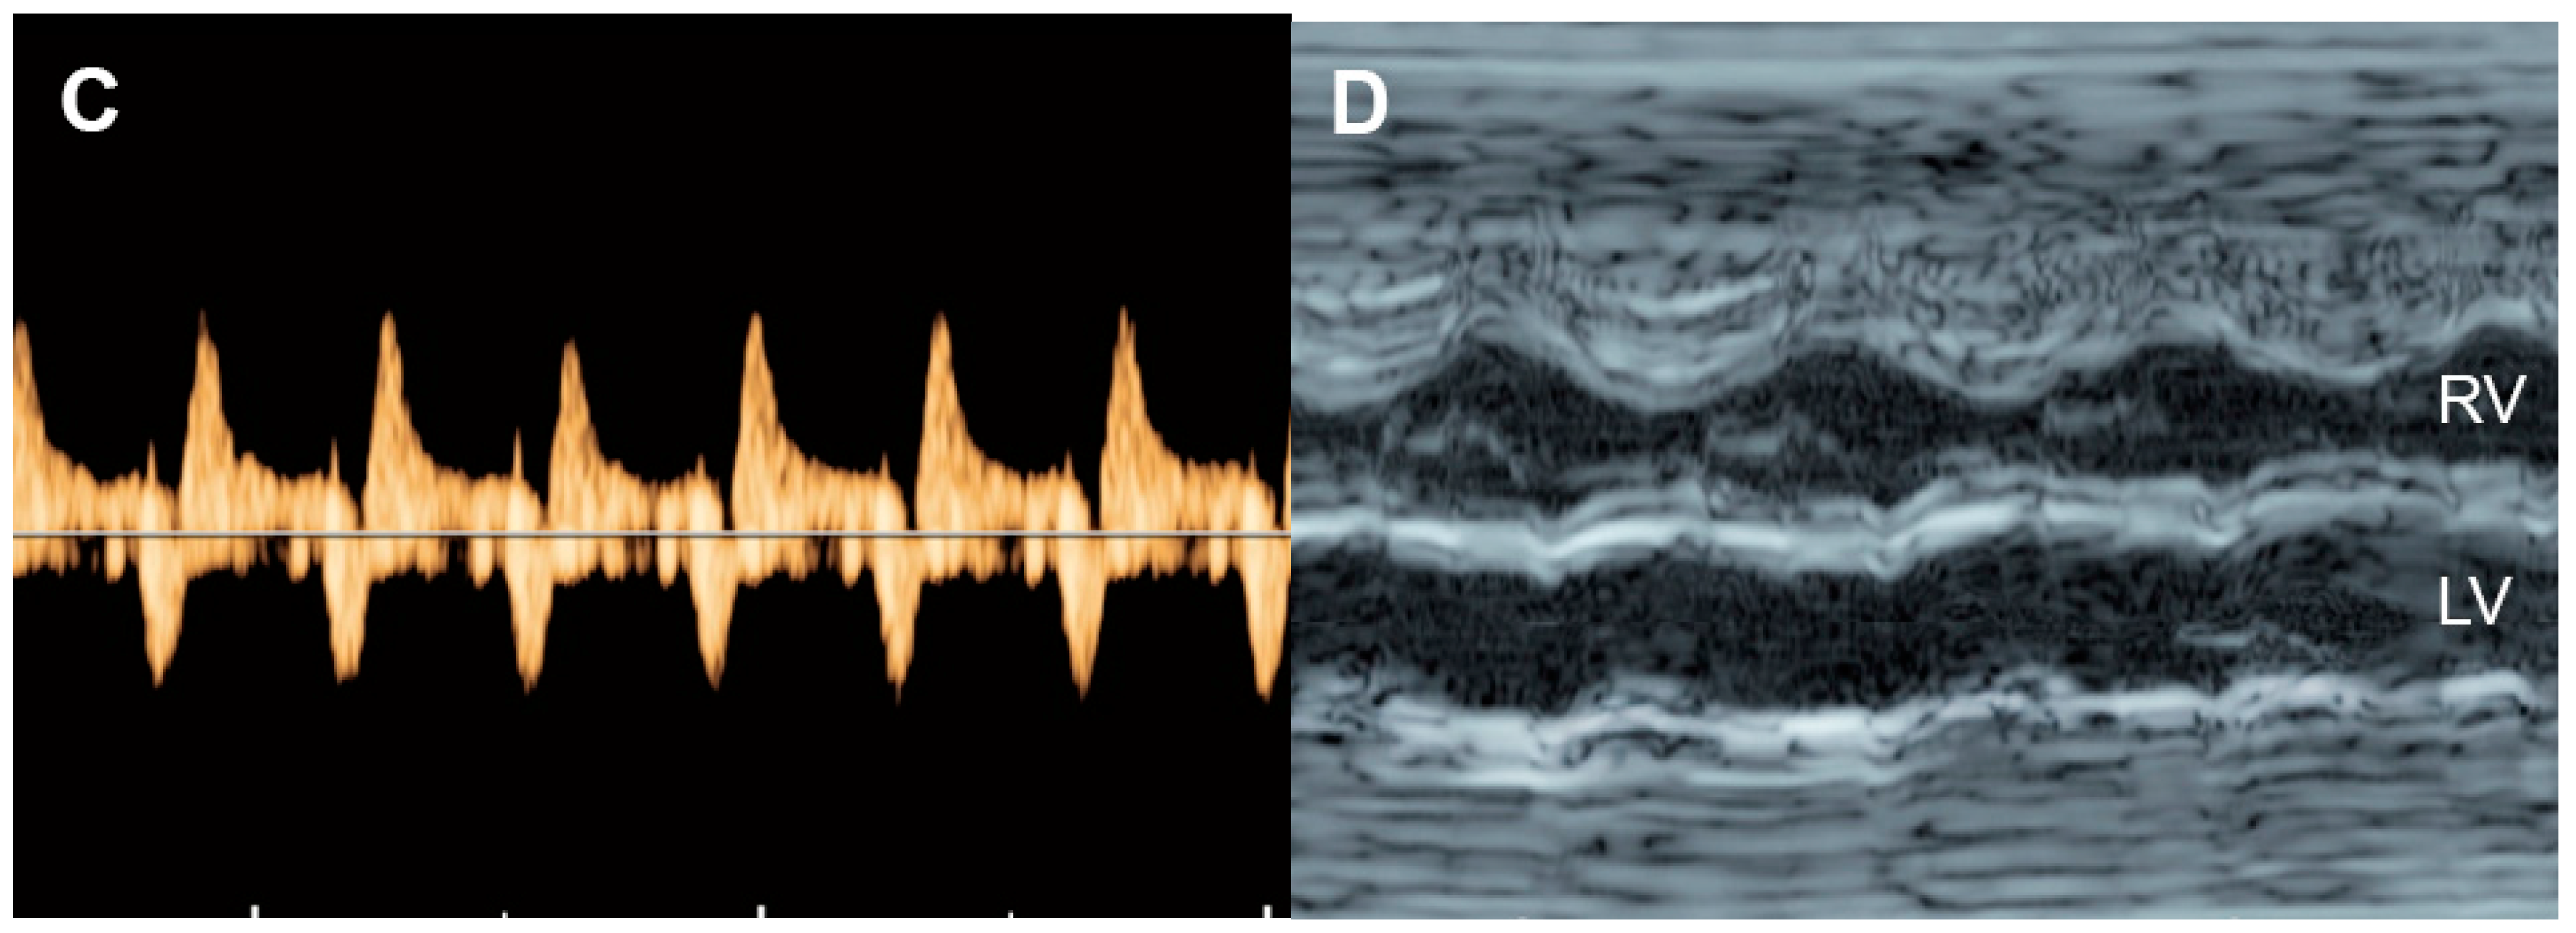

| Normal | −1 Point | −2 Points | |

|---|---|---|---|

| Hydropic signs | Absence of effusion | Abdominal or pleural, or pericardial effusion | Skin edema |

| Venous Doppler (umbilical vein: UV & ductus venosus: DV | Normal Doppler UV ![]() DV ![]() | Reversed ductus venosus flow UV ![]() DV ![]() | Pulsatile flow in the umbilical vein UV ![]() |

| Heart size (Cardio-thoracic ratio) | ≤35% | 35–50% | >50% or <20% |

| Cardiac function | Normal function | Holosystolic TR, or ventricular shortening fraction < 28% | Holosystolic MR or TR dP/dt < 400, or monophasic inflow |

| Arterial Doppler (umbilical artery) | Normal Doppler![]() | Absent end-diastolic flow![]() | Reversed end-diastolic flow![]() |